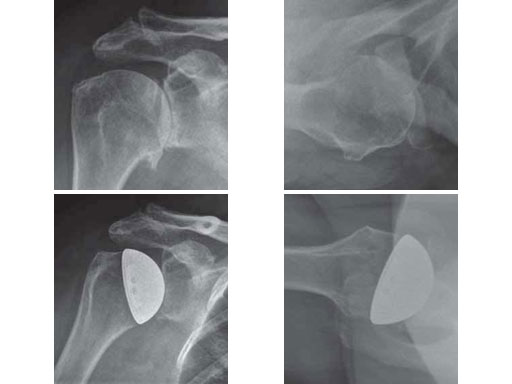

61-year-old male with a 4-part-fracture of the humeral head (head-splitting fracture).

Case provided by Norbert P Sdkamp, Martin Jaeger, Freiburg, DE, Ralph Hertel, Bern, CH

Fig 3ac Fracture situation in conventional x-rays and CT scan.

Fig 3de Implantation of a fracture prosthesis type EPOCA.